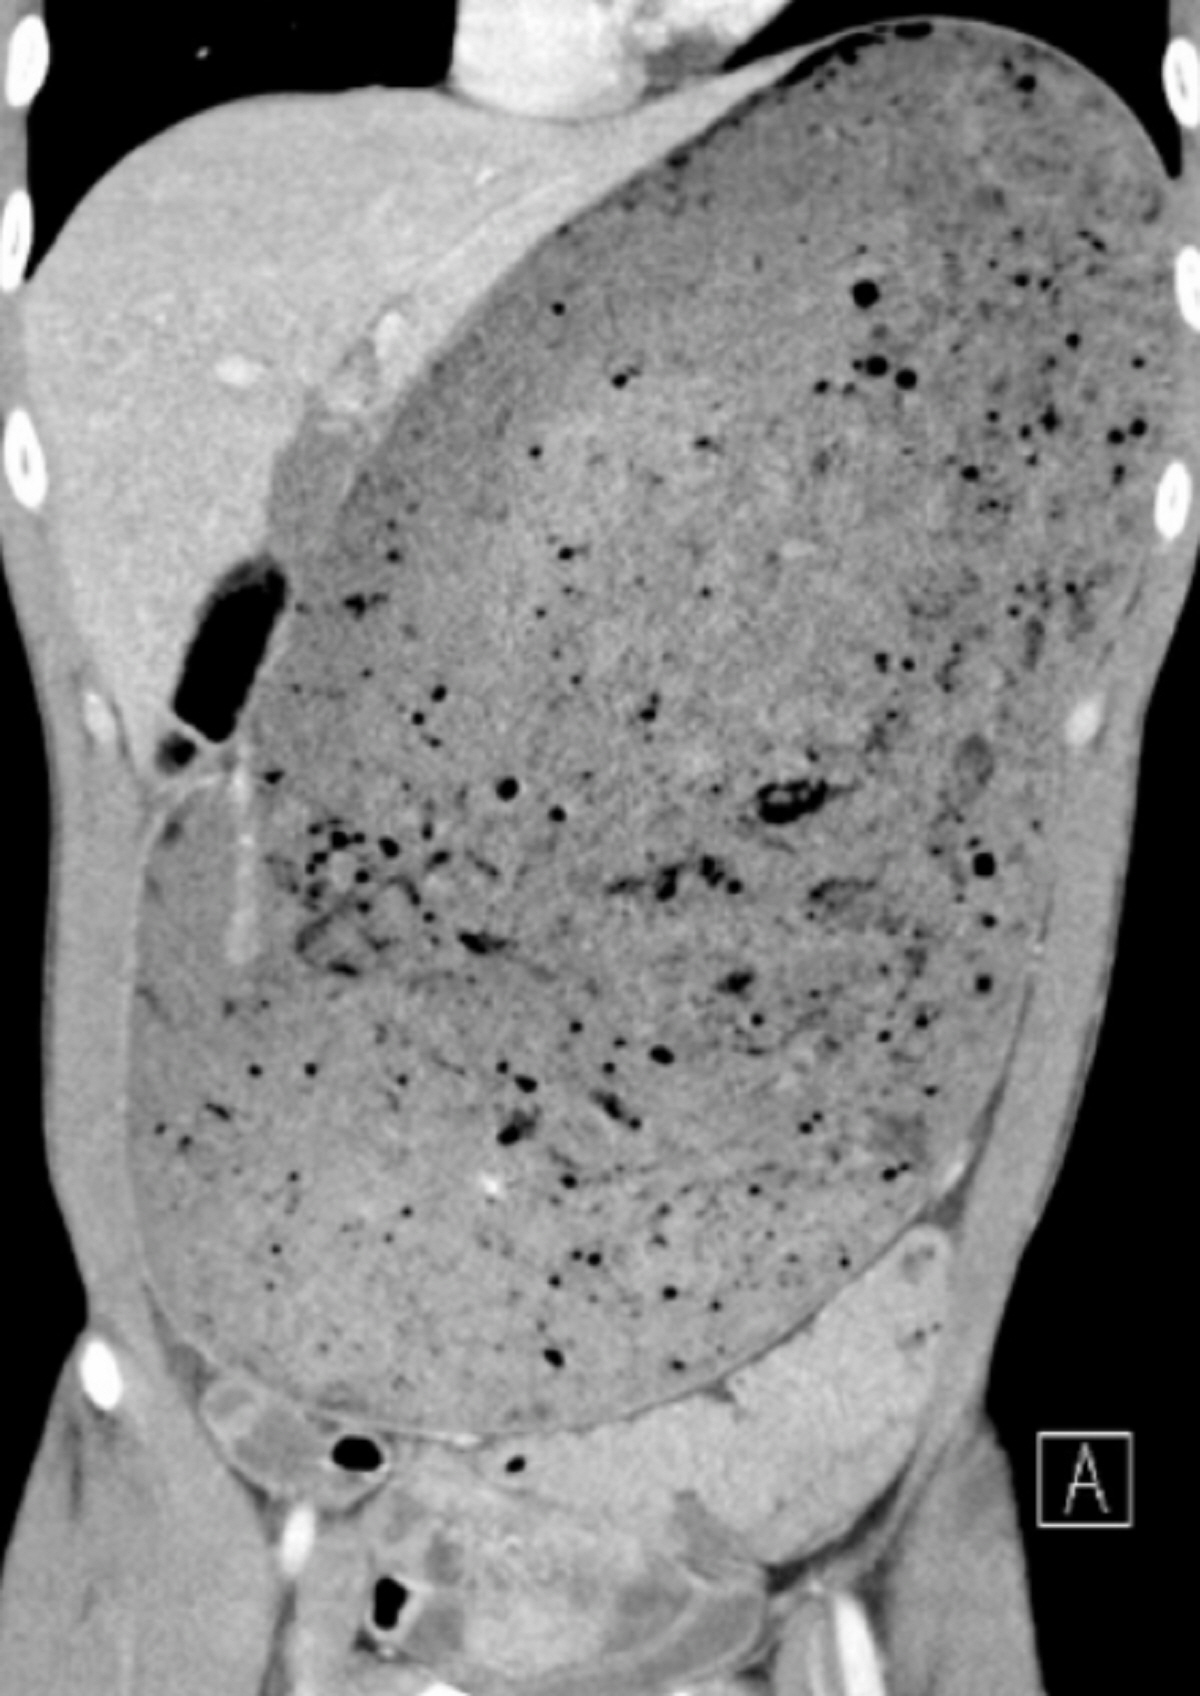

싱가포르 국립대 응텡펑 종합병원 외과 의료진에 따르면, 30세 건강한 남성이 햄버거를 빨리 먹는 대회에서 단 30분 만에 3kg에 달하는 양을 섭취했다. 몇 시간 후 그의 배가 부풀어 오르기 시작했고, 구토와 함께 통증을 느꼈다. 곧바로 응급실에 실려 간 남성은 소화되지 않은 물질로 배가 가득했고, 위는 심각하게 늘어났다. 이에 주변 장기인 췌장 역시 으스러진 것을 발견했다. 의료진은 “이렇게 위가 너무 많이 늘어나면 혈류가 차단돼 파열을 유발할 수 있다”며 “또 소화되지 않은 음식물이 복부로 누출돼 감염이나 장기 부전의 위험까지 일으킬 수 있다”고 말했다. 실제 남성의 CT 사진에는 갓난아기 크기만큼 위의 상부에 음식이 꽉 차 있던 것을 확인할 수 있었다. 의료진은 위 세척을 수행했고, 다행히 가스가 배출되기 시작하면서 체내에 있던 음식들이 이동해 그는 5일 후 퇴원할 수 있었다.